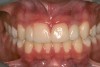

A 9-year-old girl, referred to a prosthodontic office by her pediatric dentist, presented with her mother’s chief complaint: “The kids are teasing her about her big front tooth.” Findings from radiographic and clinical examinations revealed fused maxillary central-peg lateral incisors, teeth Nos. 7 and 8, and a congenitally missing lateral incisor, tooth No. 10 (Figure 1 through Figure 3). An implant was selected as the ideal treatment to replace tooth No. 10 when somatic growth was complete. A diagnostic wax-up was fabricated to determine if the fused tooth could be made to resemble two teeth, using pink composite to give the illusion of an interproximal papilla. The patient was referred for an orthodontic consultation to plan for closure of the diastema between teeth Nos. 8 and 9 and achievement of proper alignment for implant No. 10. The patient was also referred to a periodontist for pretreatment assessment of the tooth No. 10 site. An endodontist was consulted should exposure of the large pulp occur during tooth preparation.

Fig 1 and Fig 2. Pretreatment photographs. Patient at 9 years of age on presentation.